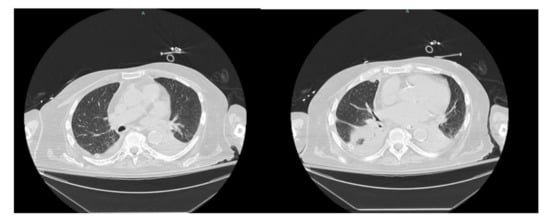

His hospital course was subsequently complicated by new onset and worsening respiratory distress on day eight of hospitalization requiring re-intubation. Repeat CT chest showed diffuse narrowing of the left mainstem bronchus, occlusion of right posterior segmental bronchi with atelectasis, complete collapse of the left lower lobe due to occlusion of left lower lobe central bronchi with trace right pleural effusion (Figure 6).

Figure 6. CT chest showing diffuse narrowing of the left mainstem bronchus with trace right pleural effusion.